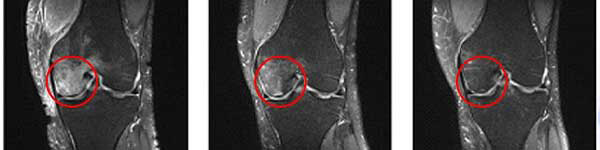

Guarda come Lidia ha curato le sue ginocchia in 7 giorni:

Ha detto: “Per molto tempo ho avuto un intenso dolore all'articolazione del ginocchio sinistro. Per questo motivo, c'erano difficoltà nel movimento. Sono andata da uno specialista, mi è stato diagnosticato un edema al femore sinistro. Si sono offerti di eseguire un'operazione al ginocchio, ma ero molto spaventata dalla procedura durante la quale si inserivano gli aghi dentro il corpo. Fortunatamente, ho incontrato Leonardo e ho iniziato ad usare Cannabis Oil appena in tempo. Dopo 3 giorni il dolore è completamente scomparso e una settimana dopo camminavo già senza dolore e ha iniziato a fare nordic walking seguendo la moda. La foto mostra il risultato dei miei progressi.”